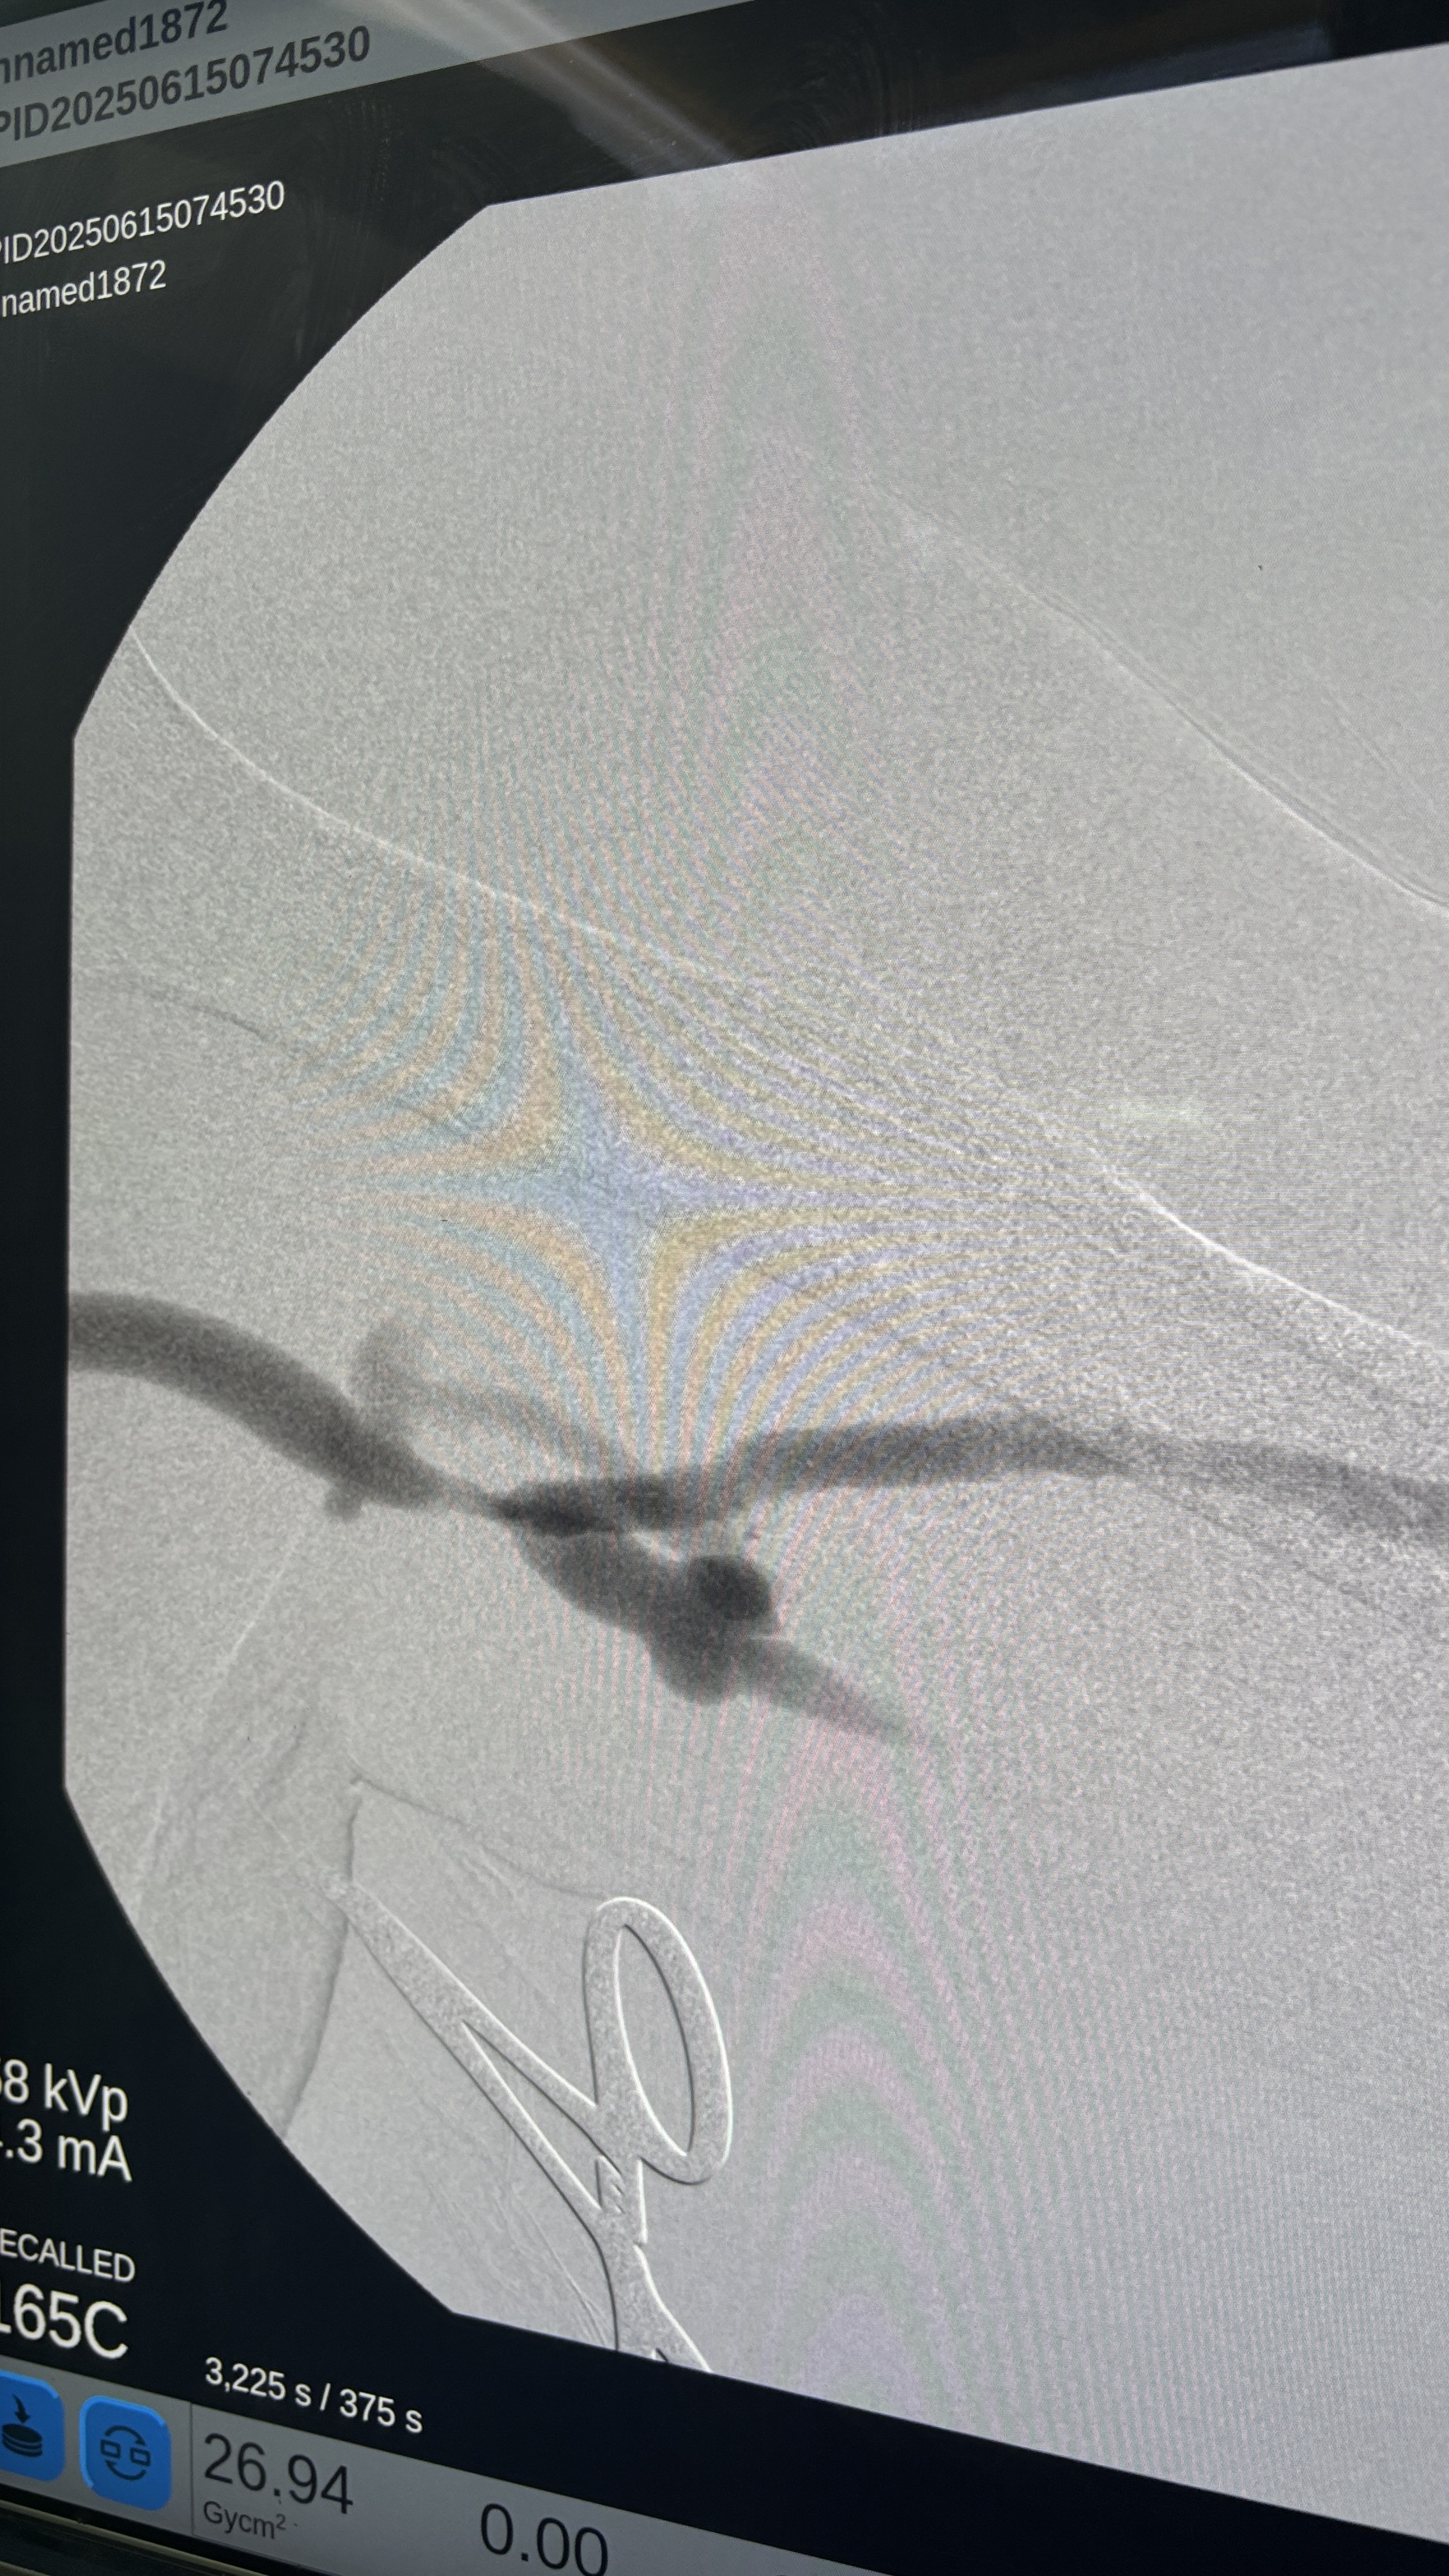

迅速且確實的ACLS,還好病人有ROSC,不過葉克膜放到一半,找了兩個6Fr sheath先建立管路,如果真的有需要,就可以直接換成ECMO

下午開了一個Thrombectomy + PTA,是個可愛的阿公,雖然一直問我刀是要開完了沒,不過開完刀露出來的笑容還真是可愛,讓我想到我自己的阿公,我握著他的手跟他說保重,就跟我之前會跟阿公說的一樣